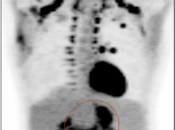

In general, we raise a suspicion of gastric malignancy if:

• Focal or regional hypermetabolic activity is accompanied by at least the suggestion of associated wall thickening (often difficult to assess if the patient’s stomach is suboptimally distended with water or oral contrast);

• Uptake is extremely focal (more likely to represent malignancy or ulcer);

• Focal/segmental uptake is extremely intense.

• Obviously, signs of associated metastatic disease on the scan give the radiologist much greater confidence in reporting a suspected primary gastric lesion.